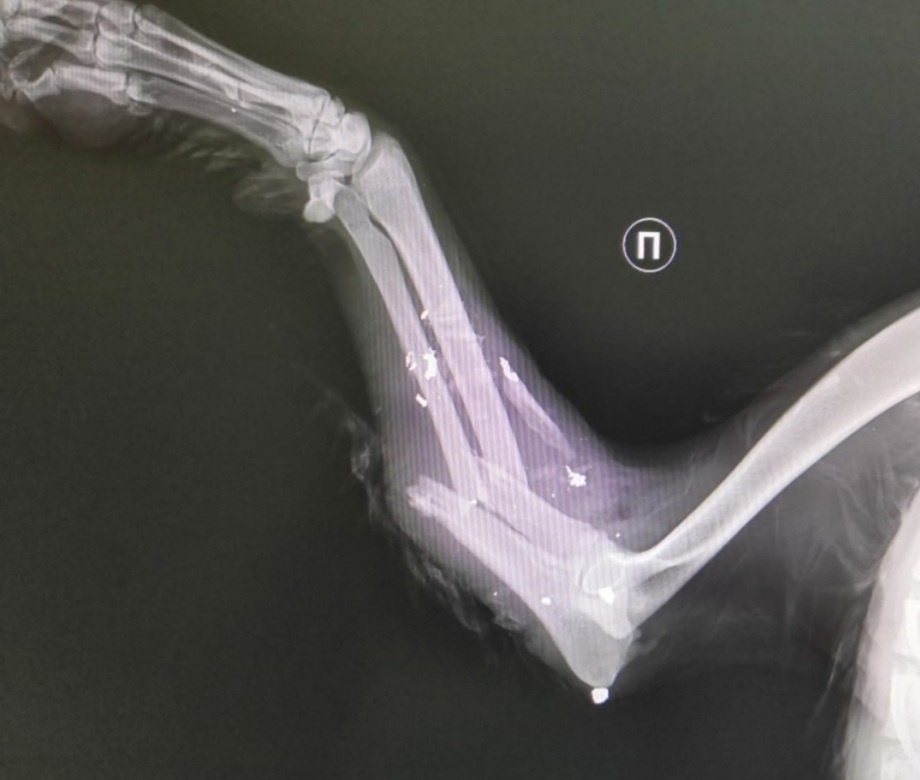

Может ли один рентген обнаружить перелом

Мне понадобилось пять, и то без компьютерной томографии не обошлось. Сегодня провела ночь без сна. Плакать сил нет, просто лежала с закрытыми глазами, в палате ещё три женщины. Нахожусь в реабилитационном центре больницы на реабилитации после перелома колена, лечусь уже десятый день. Про коленку я уже и забыла, сломала её четыре месяца назад, а вот оперерированный тазобедренный сустав беспокоит, болит после падения. Шейку бедра я сломала два года назад, сделали тотальное эндопротезирование, дело шло на по правку, и тут колено. Конечно когда гипс накладывали сразу сделали и рентгеновский снимок бедра. Всё в порядке, всё на месте, а болит. После того как сняли гипс с колена ещё один снимок в травмпункте, всё хорошо, протез на месте, а оно болит. Врач сказал, что у меня растяжение от гипса получилось, две недели покоя, а потом усиленно коленку разрабатывать. Коленку я разработала, вертится под любым углом, только вот тазобедреннный сустав болит. Поехала к другому травматологу, ещё один

Про коленку я уже и забыла, сломала её четыре месяца назад, а вот оперерированный тазобедренный сустав беспокоит, болит после падения. Шейку бедра я сломала два года назад, сделали тотальное эндопротезирование, дело шло на по правку, и тут колено. Конечно когда гипс накладывали сразу сделали и рентгеновский снимок бедра. Всё в порядке, всё на месте, а болит. После того как сняли гипс с колена ещё один снимок в травмпункте, всё хорошо, протез на месте, а оно болит. Врач сказал, что у меня растяжение от гипса получилось, две недели покоя, а потом усиленно коленку разрабатывать. Коленку я разработала, вертится под любым углом, только вот тазобедреннный сустав болит. Поехала к другому травматологу, ещё один снимок, и опять всё замечательно. И вот через четыре месяца после перелома колена пришла на реабилитацию, при поступлении сделали ещё один рентген, всё как и, положено стоит на своих местах. Началось обычное лечение, много лечебной физкультуры, массаж, капельницы.

Действитнльно реабилитация. Дома я конечно тоже делаю упражнения, но здесь под руководством инструктора, меня уже никто не жалеет, как я себя сама, и приходится делать со слезами. И даже как-то хуже стало, но это обычное явление. Даёшь нагрузку на мышцы, они не разработанные, конечно устают и болят. Но у меня как-то другая боль, как при переломе. Упросила врача вызвать мне для консультации ортопеда. Доктор и не понял, что я от него хочу. Коленка не болит, снимок хороший, но ведь болит. И главный вопрос у меня - разрабатывать мне дальше ногу через слезы и боль, или оставить в покое, а вдруг там что-то сломается или оторвется. Приглянулся доктор получше, позвал лежащего врача.

- Вроде перелом на снмке видно, но она режим покоя не соблюдала.

Конечно не соблюдала, у меня же ничего не было, я усиленно физкультуру делала. Вынес доктор вердикт - срочно сделать компьютерную томографию, исходя из неё будет принимать решение.

Мне видимо придётся долго ждать,а потом догонять, что упустила и во время не начала лечение перелома. И сколько нужно было сделать рентгеновских снимков, чтобы получить окончательный результат.